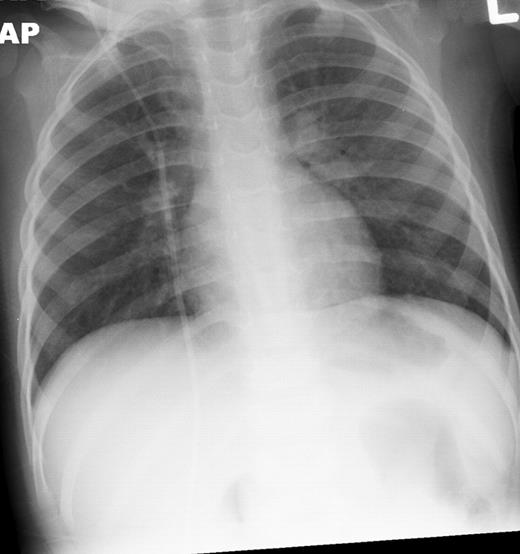

Our Patient, 8 weeks into chemotherapy for newly diagnosed ALL, presented with high grade fevers and poor activity. Patient was admitted 3 weeks prior for Bacillus cereus bacteremia. Additionally the patient had been on broad spectrum antibiotics on 2 occasions for febrile neutropenia episodes within the past 2 weeks. Patient had minimal respiratory symptoms at this presentation and recovered from pancytopenia at the time of this presentation. CT scans and chest x-ray (Figures 1 and 2) showed diffuse marked ground glass opacities with dependent consolidation in the lungs. On day 3 of admission, bronchoalveolar lavage (BAL) was preformed and empiric trimethoprim-sulfamethoxazole was initiated in addition to broad spectrum antibacterial, antifungal and antiviral medications.